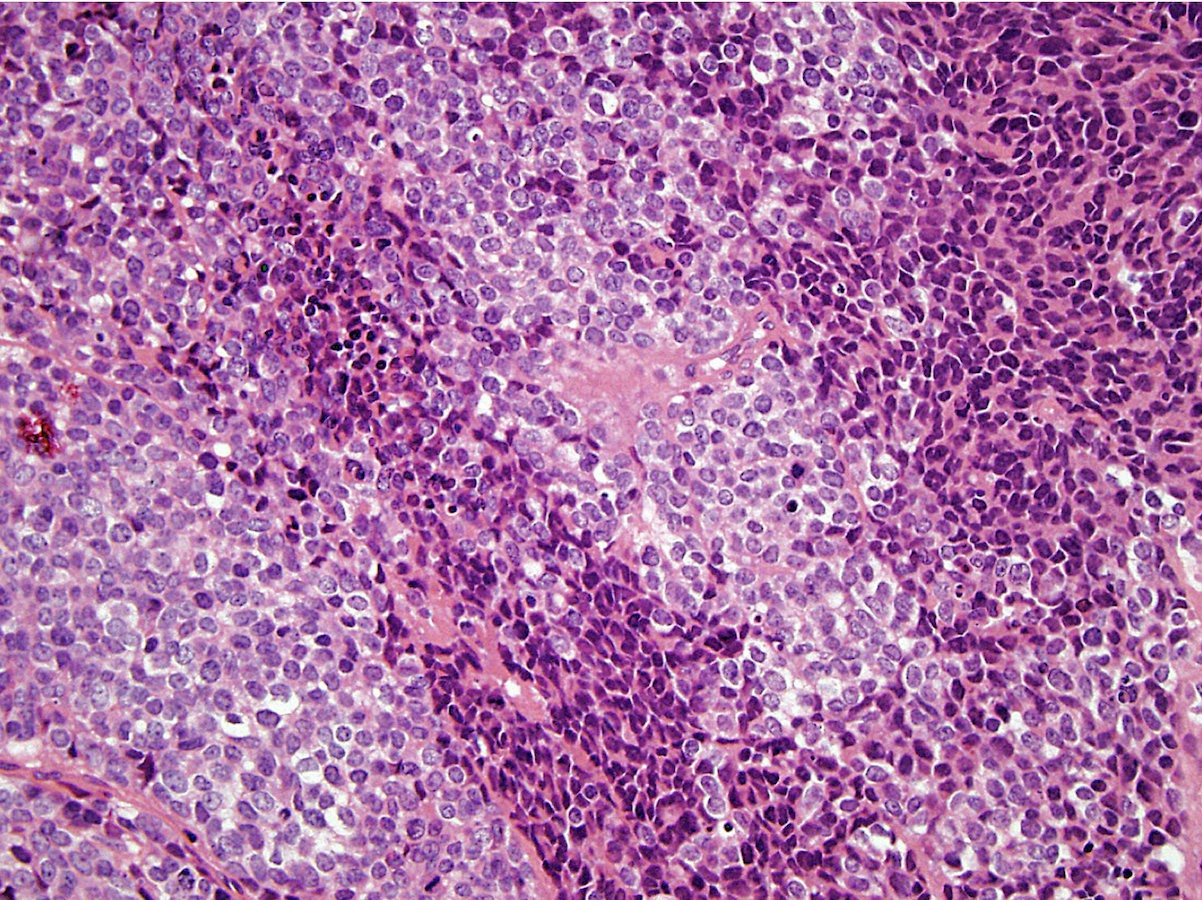

Microscopic (histologic) description

- Classical Ewing sarcoma (Virchows Arch 2009;455:397)

- Sheet-like growth pattern

- Islands separated by dense fibrous tissue

- Subset with neuroectodermal differentiation (Homer-Wright pseudorosettes)

Microscopic (histologic) images